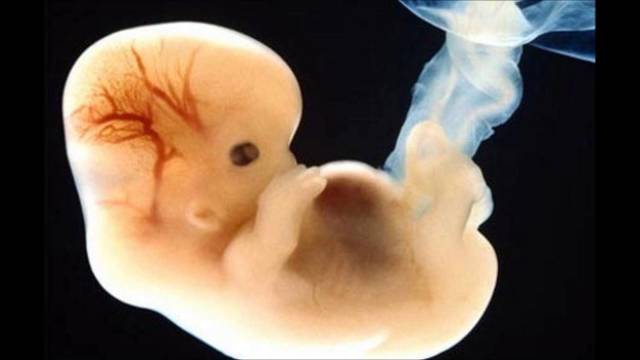

Periodo embrionario

El embrión es considerado a partir de la 4ta semana de gestación y hasta la 8va semana de gestación

Ocho semanas son el marcador del fin del período embrionario.

Durante esta etapa, el embrión humano se ha desarrollado desde una única célula hasta los casi mil millones de células que forman más de 4 mil estructuras anatómicas distintas. A partir de aquí ya recibe el nombre de feto.

El feto ahora posee más del 90% de las estructuras que se encuentran en los adultos.